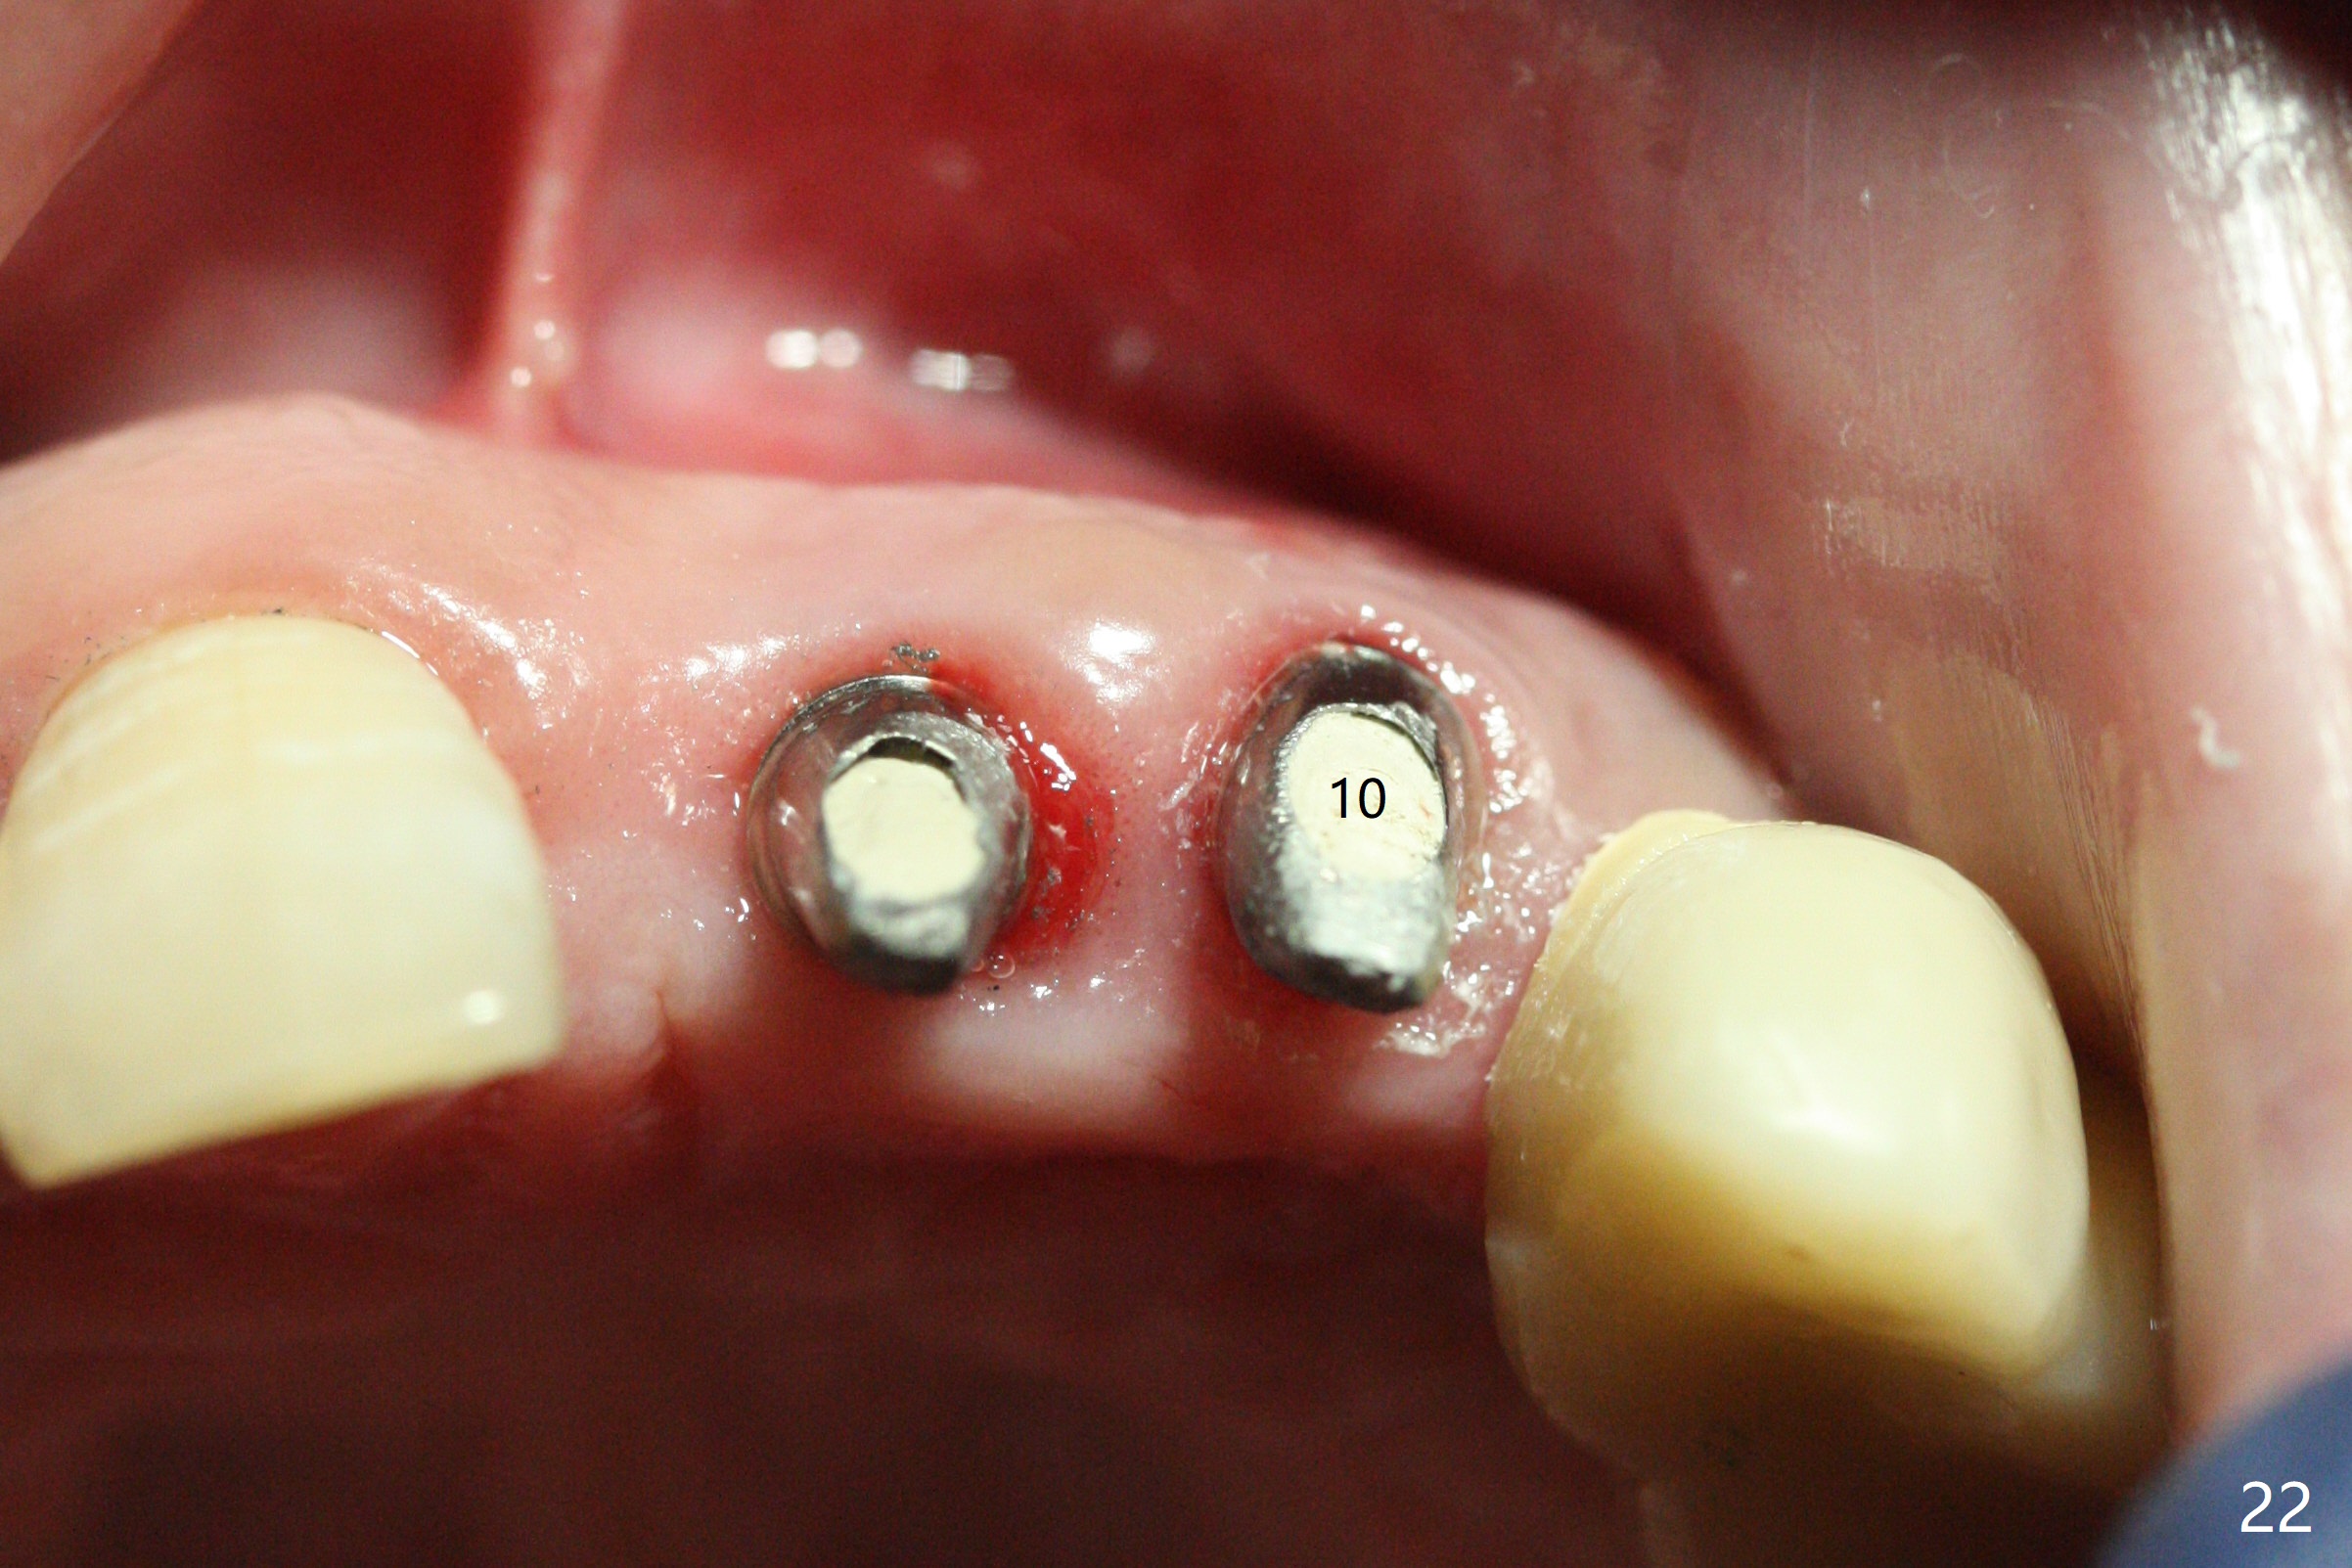

There is 1-2 thread exposure mesial and distal at #10 two years postop (Fig.20'), which may be related to the small fistula labially (Fig.20 >). It appears that the implant at #10 was placed too high (Fig.21) and labially (Fig.22). In fact the bridge fractures between #12 and 13 during pandemic.